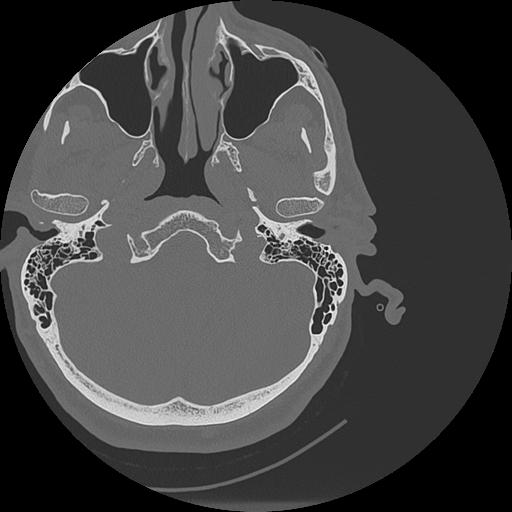

7 HUESO,,Vol,0.5,HUESO,,